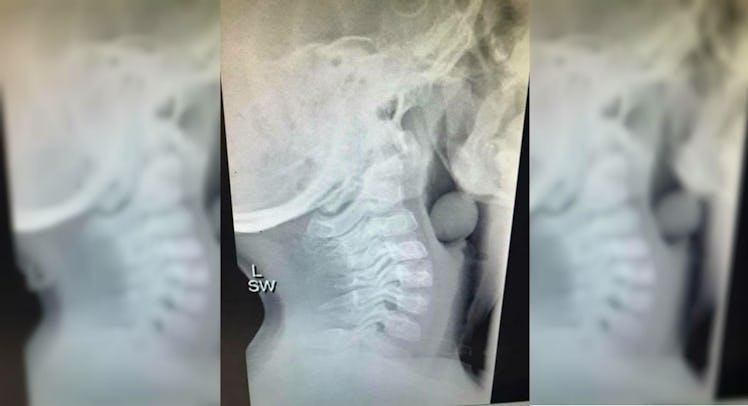

An X-ray image of a grape stuck in a 5-year-old’s airway is going viral after one mom shared the picture on her Facebook page. Morbid fascination aside, the image should serve as a wakeup call for parents who let their toddlers eat small foods—especially since a young child’s airway is about the same size as a whole grape.

When it comes to food (which accounts for about half of all choking hazards in children) grapes are among the most dangerous, according to a study published in Archives of Disease in Childhood. The study was published after five separate incidents of kids choking on grapes were reported. Two of those incidents resulted in death. In the case of this particular image, the child in question was rushed to the emergency room and the grape was successfully removed.

“This sweet soul had to be operated on, under general anesthetic to remove the grape,” the mother wrote. “He is VERY lucky that part of his airway was open or else this could have ended badly. So please be mindful that not all kids chew their food.”